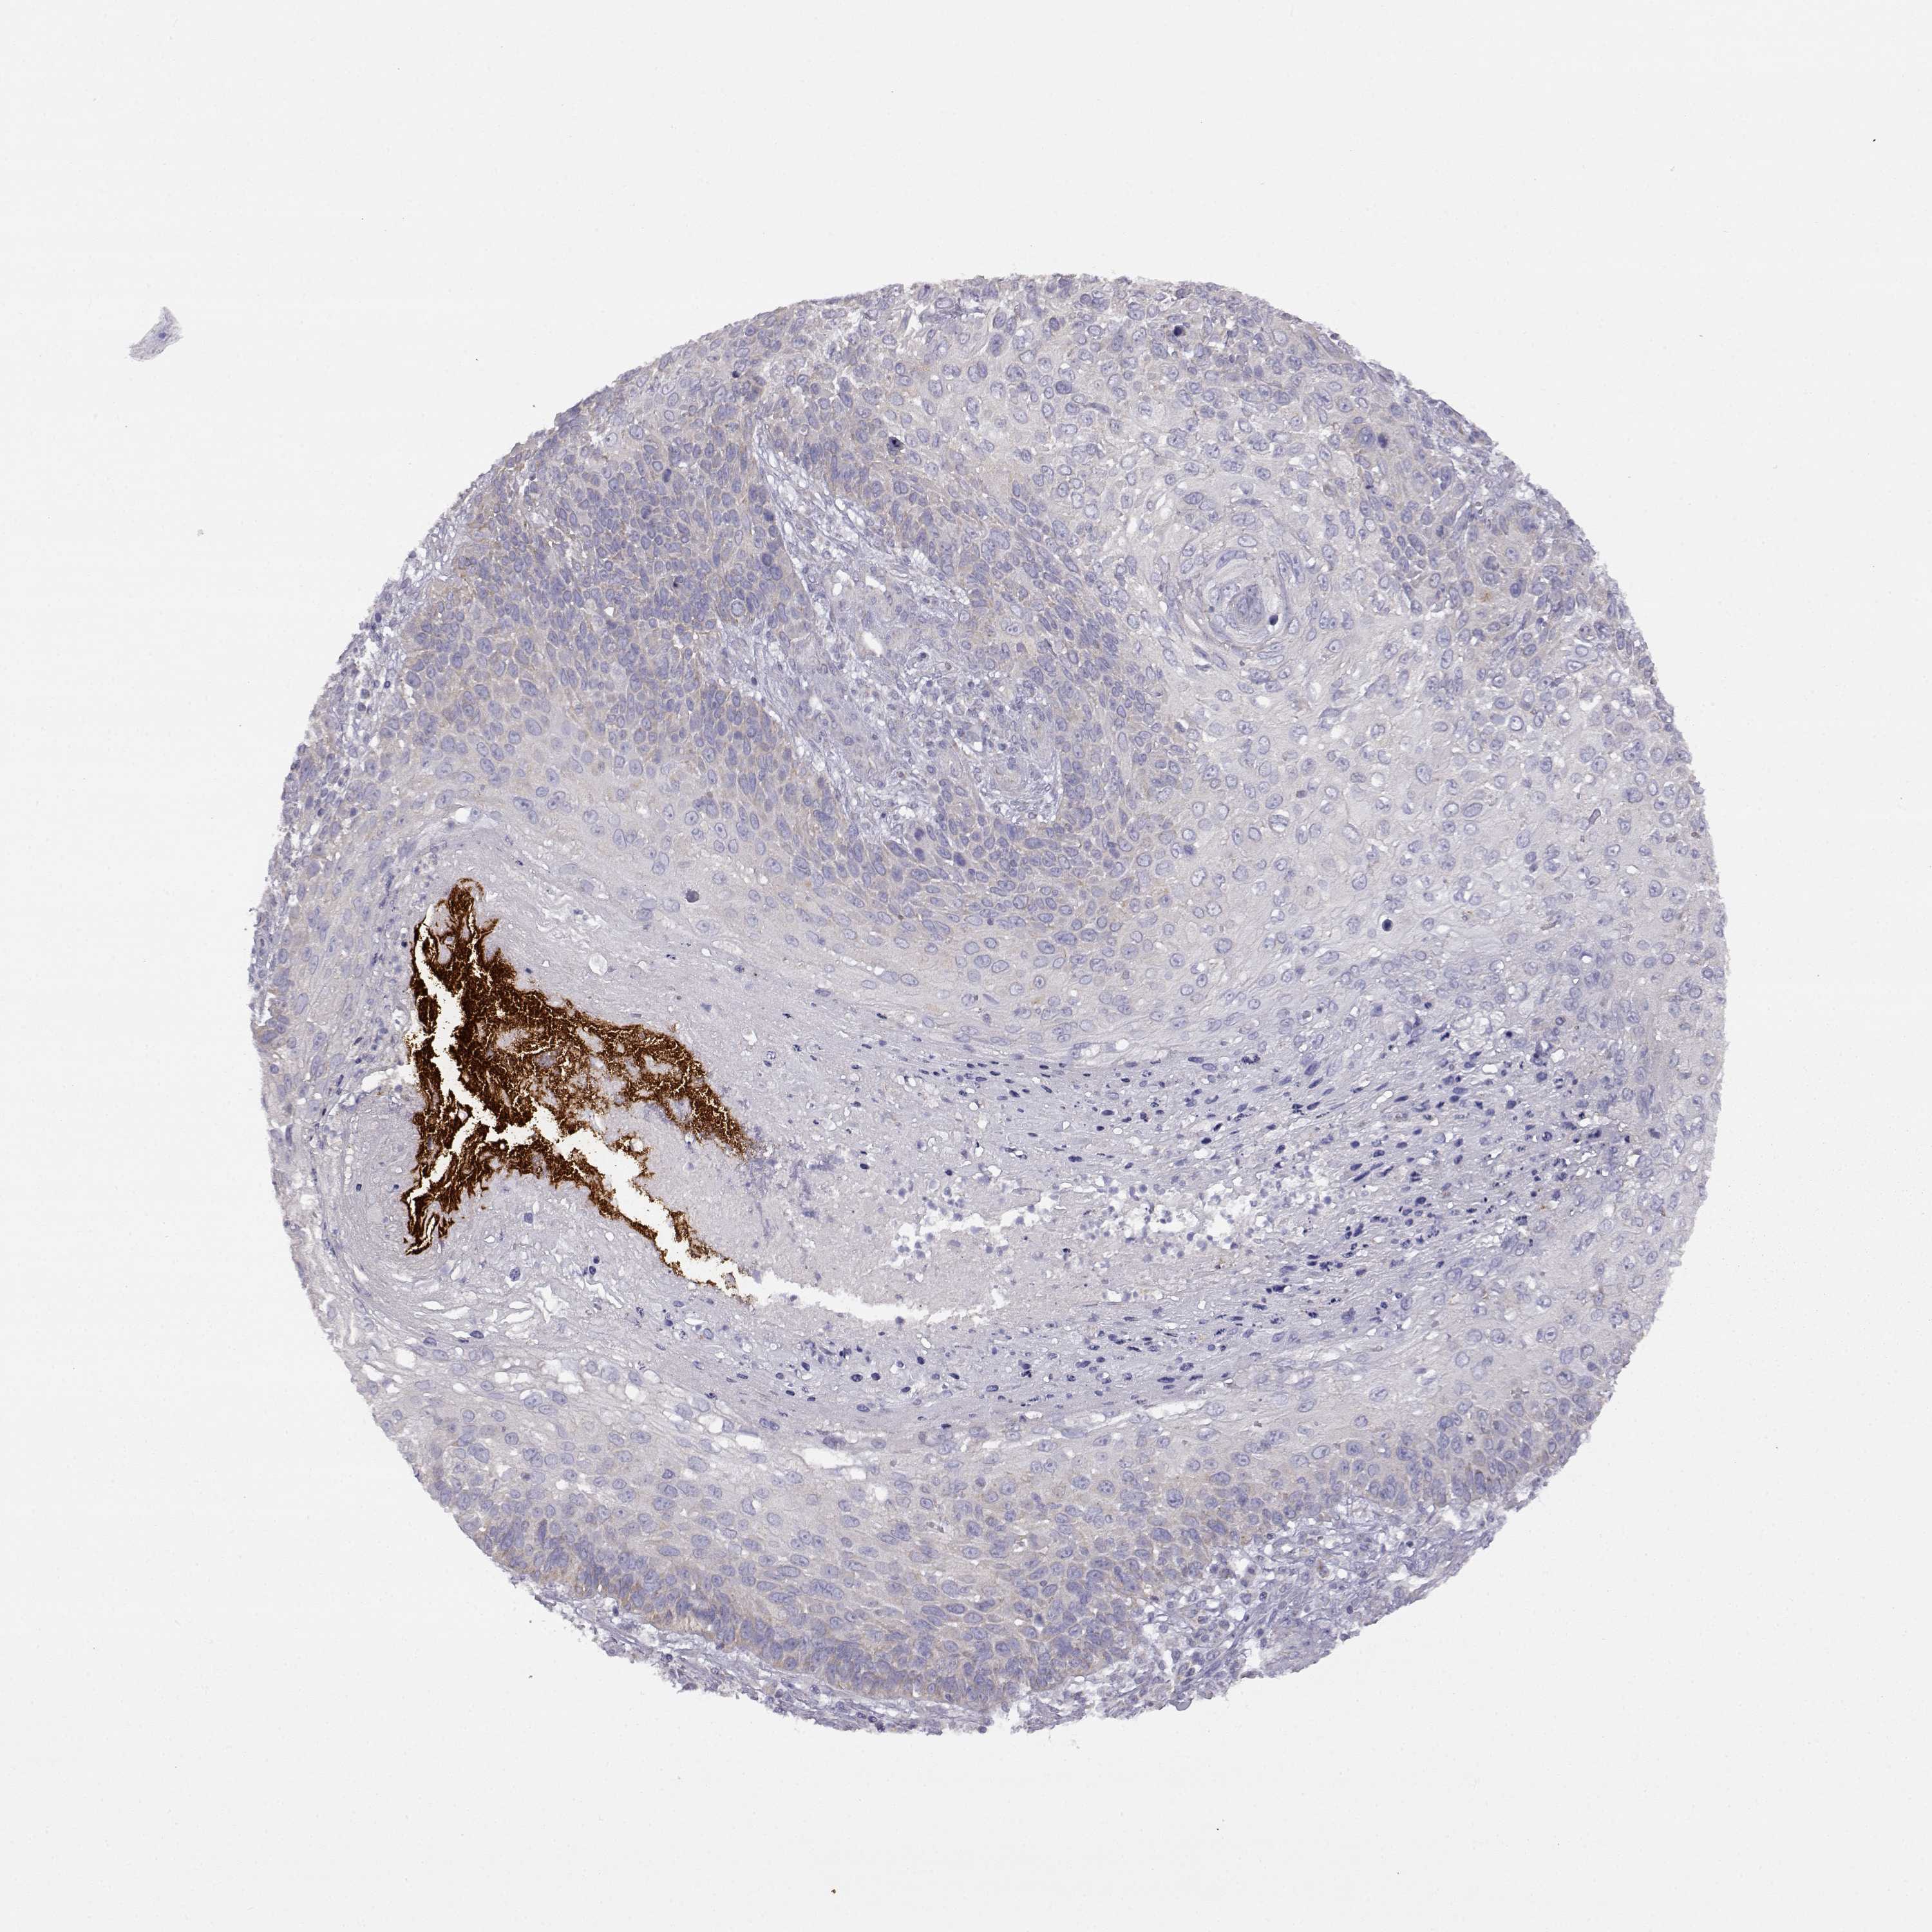

Basal cell and squamous cell cancer

SKIN CANCER - Protein expressioni

A mouse-over function shows sample information and annotation data. Click on an image to view it in a full screen mode. Samples can be filtered based on level of antibody staining by selecting one or several of the following categories: high, medium, low and not detected. The assay and annotation is described here.

Antibody stainingi

Antibody staining in the annotated cell types in the current human tissue is reported as not detected, low, medium, or high, based on conventional immunohistochemistry profiling in selected tissues. This score is based on the combination of the staining intensity and fraction of stained cells.

Each image is clickable and will lead to virtual microscopy that enables deeper exploration of all samples and also displays staining intensity scores, fraction scores and subcellular localization as well as patient and tissue information for each sample.

Antibody HPA017742

Staining

High

Intensity

Strong

Location

Nuclear

Cytoplasmic/membranous

Basal cell carcinoma

Squamous cell carcinoma, NOS